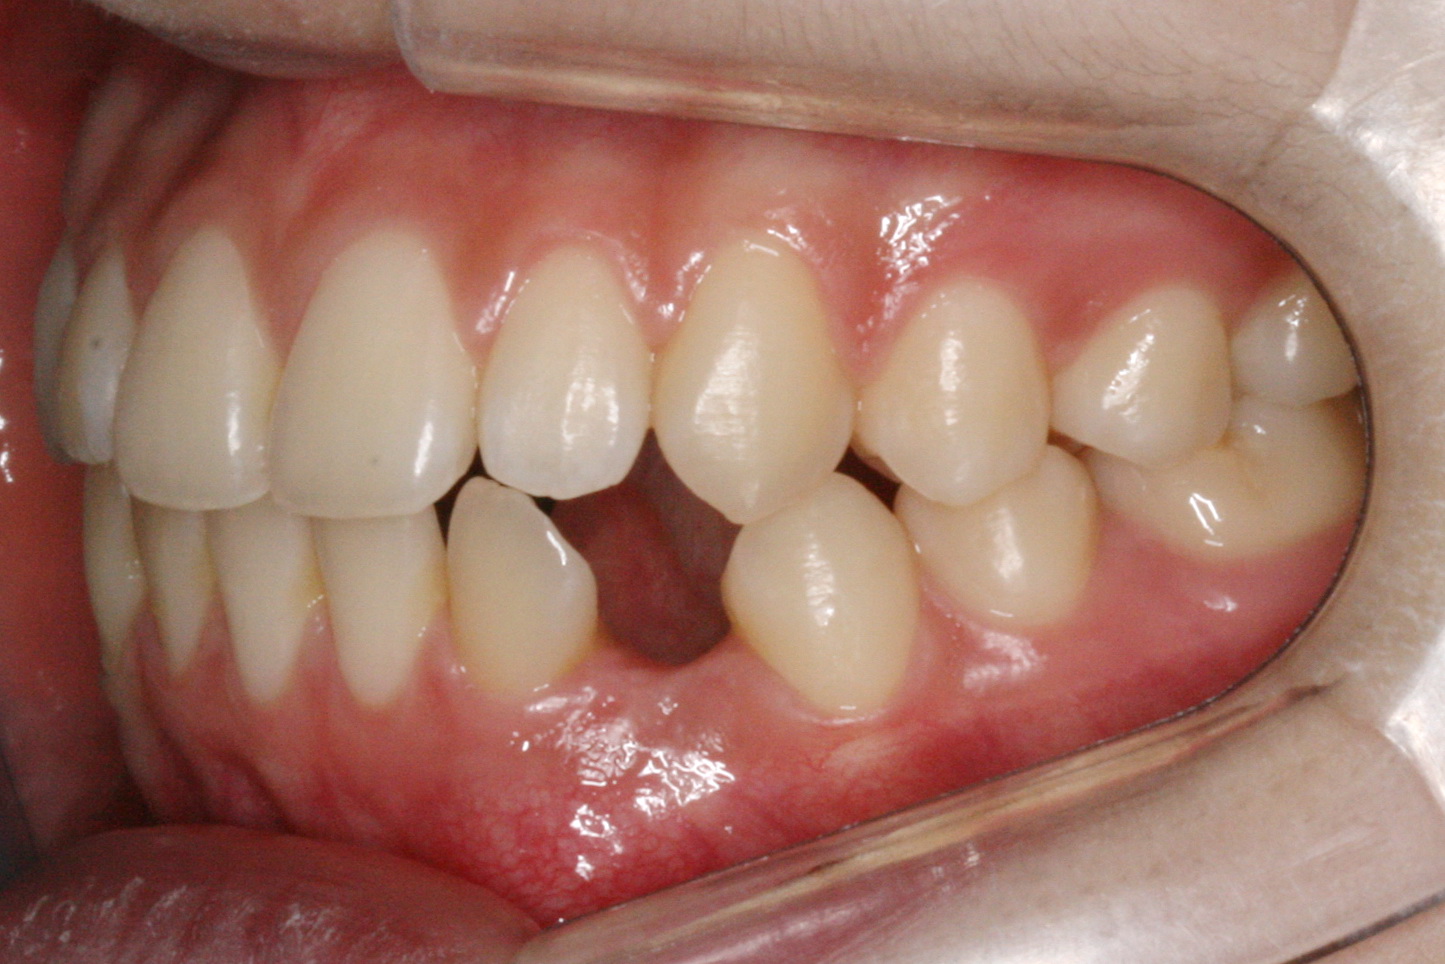

맹출유도교정

보철교정